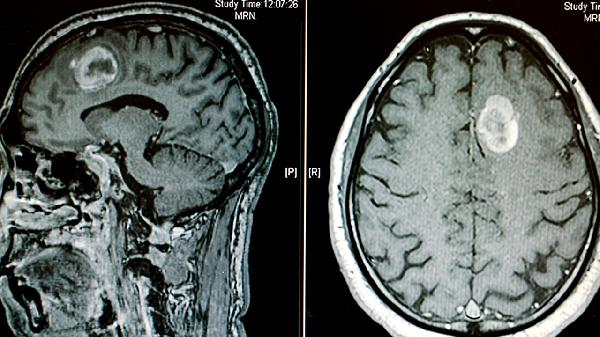

脑CT检查是临床常用的影像学检查手段,通过X射线对人体头部进行断层扫描,能够清晰显示脑组织结构。单次脑CT检查的辐射剂量约为2-10毫西弗,远低于可能致癌的100毫西弗阈值。现代CT设备采用智能剂量调节技术,可根据检查部位自动优化辐射剂量,进一步降低风险。对于需要重复进行脑CT检查的患者,医生会严格评估检查的必要性,确保累积辐射剂量在安全范围内。